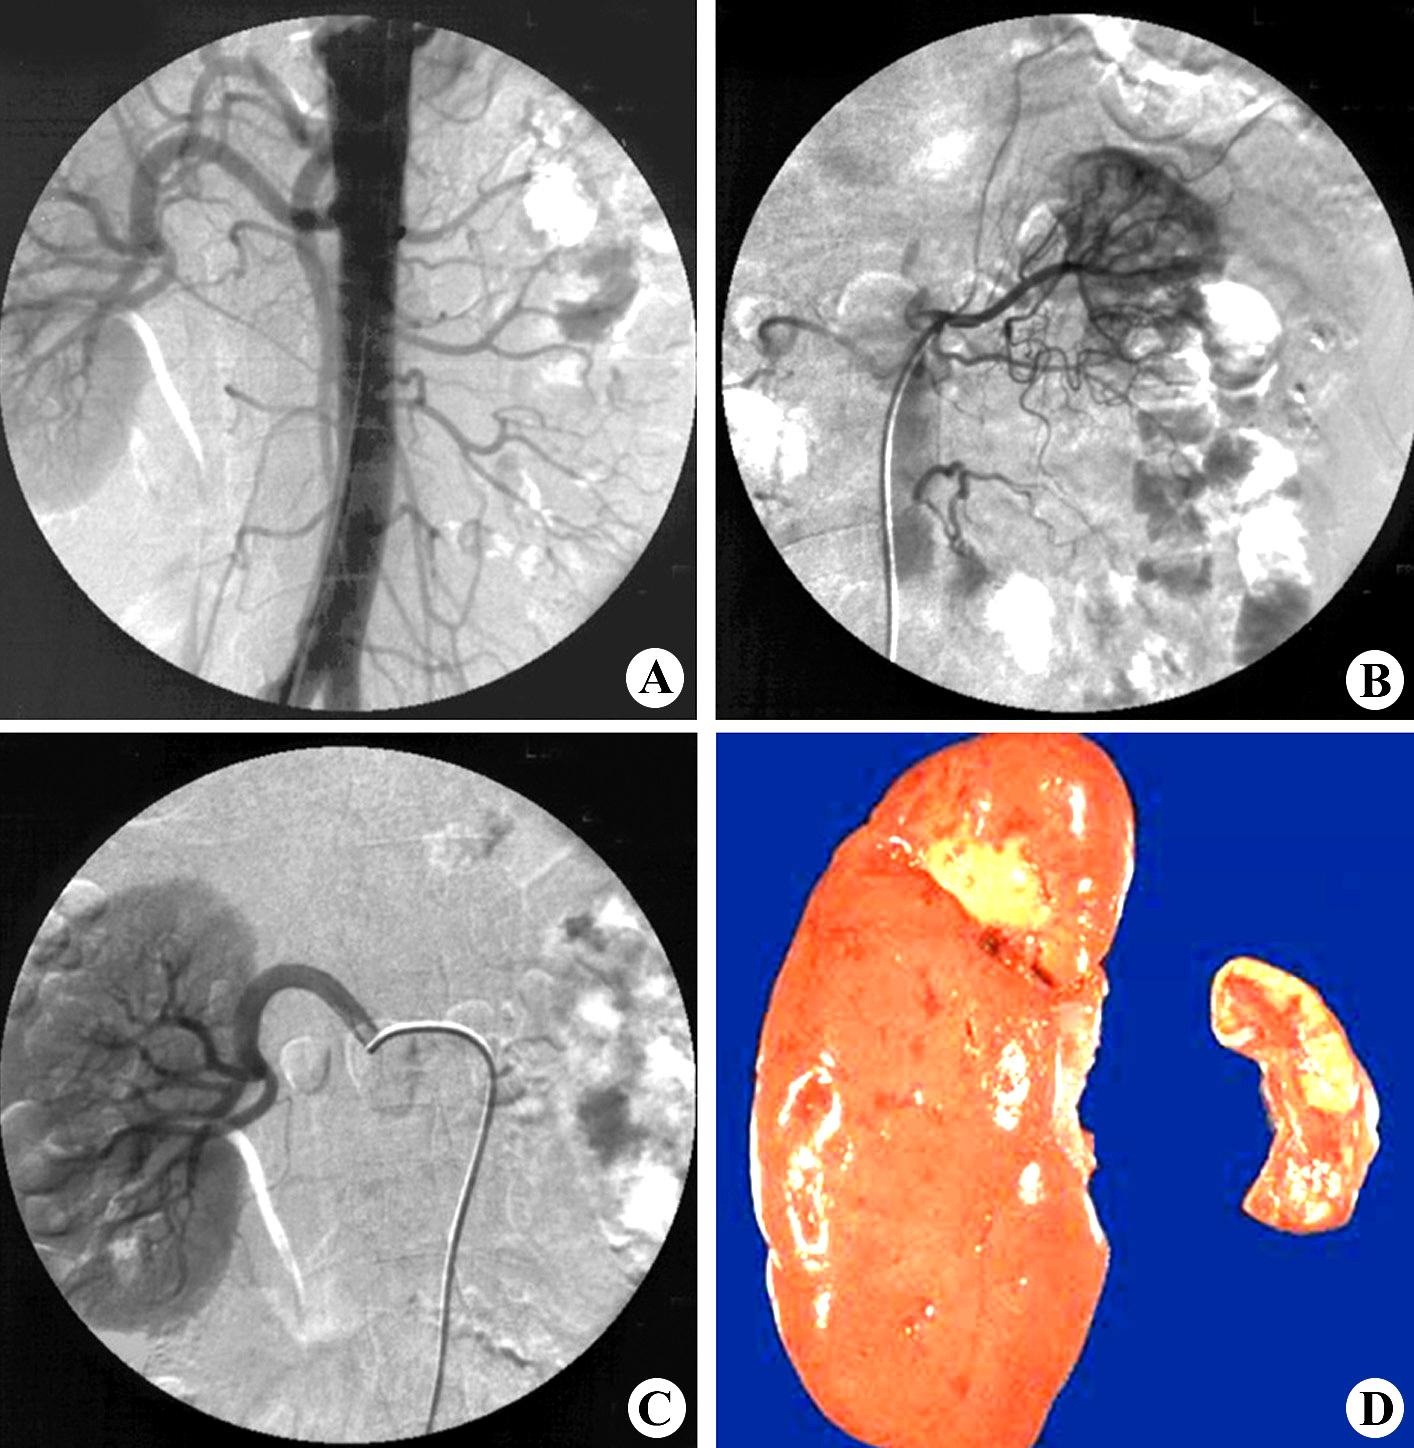

右肾影缩小,呈分叶状图6-45:右肾萎缩,左侧肾盂输尿管积水ctct平扫(a